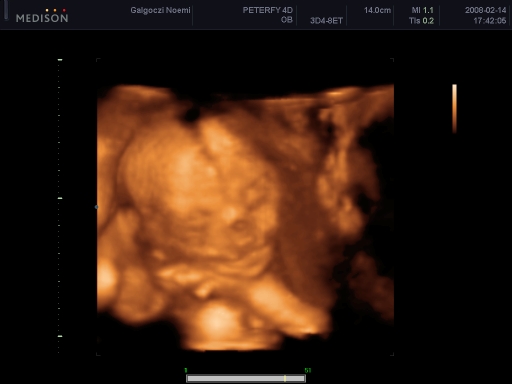

4 D-s ultrahang

Tegnap voltunk! Szuper volt, bár igaz, hogy csúszás volt, de vittem könyvet Bencének, és egész jól bírta!

Szóval:Csillához hasonlóan nekem is az AFP miatt kellett mennem, és tökéletesen egészséges. Borzasztóan ficánkolt! Bence pedig ott fekhetett mellettem, és együtt néztük! :)

Csak 2 D-n mutatta a kukiját, a másikon összezárta a lábát.

Boxolt, ivott a magzatvízből, pisilt, ásított, de szemből nem akarta megmutatni az arcát, mindig odakapta a kis kezét. Súlya: 356 g, fejecskéje 18 cm körben, pocija 15, combcsontja 3,3, ha jól emlékszem!

Összesen 27 db fényképet csináltak cd-n, ebből 1-et kaptunk nyomtatva is, és az egészről kaptunk egy dvd-t, ami 25-30 perc.

Kép

Itt a pofija látszik, a két keze, és bal oldalon felül a jobb talpacskája a feje tetején.

Levi ásít

Az egyik keze az álla alatt, a másikkal fogja a fejét

Olyan, mintha az alsón nem lenne orra! Én parázok egy kicsit, de állítólag csak valami árnyék miatt látszik így, és biztos kiszúrták volna!